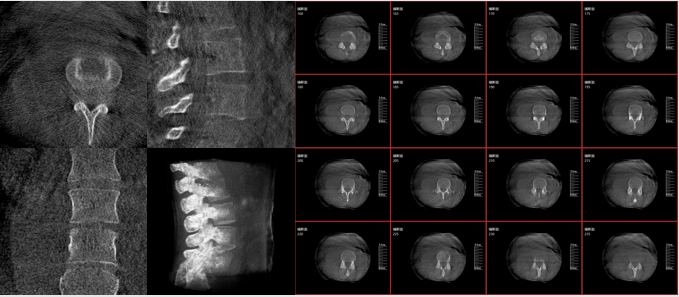

術中三維影像

而三維影像的MPR圖像組可以通過不同平面的切分,使成像區內更豐富的信息得以呈現。尤其是二維影像無法涉及的橫斷面,提供了另一個空間維度的信息量。

作為使用者,醫生在手術中雖然有術前的影像作為判定依據,但每一臺手術都具有獨特性,需要術中三維影像提供的實時信息,作為術中診療操作的基礎。

在MPR圖像中,冠狀面、矢狀面和橫斷面的信息大大提高了醫生對于病灶區以及手術效果的判定。